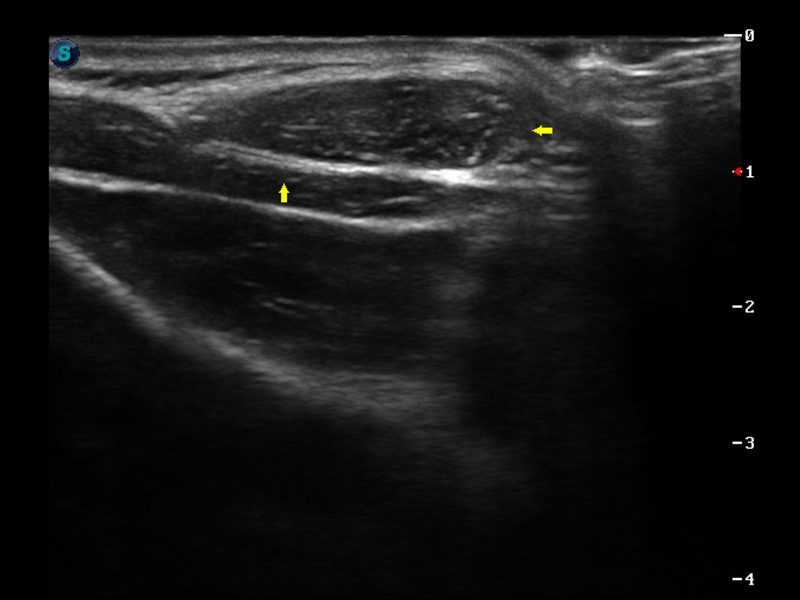

S9便携式彩色多普勒超声诊断仪是云顶集团官网研发的高端便携彩超设备,外观设计新颖、产品性能卓越。S9在便携超声领域采用了突破传统的触摸屏交互设计,并以先进的软件硬件技术和设计理念,为您带来清晰的图像质量、稳定的工作性能和便捷的操作体验。

实时宽景成像